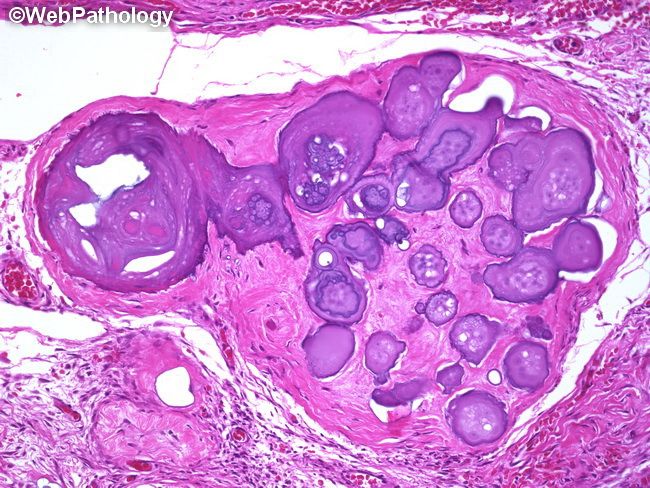

Папиллярный некроз